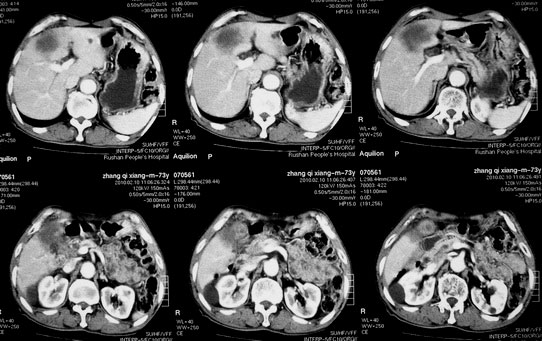

肝胆管细胞癌

患者AFP正常,无肝病病史。CA199 1000ng/ml,CEA偏高。血象WBC正常,N偏高。

化脓性胆囊炎累及肝脏;胆管细胞癌;肝转移瘤

活检病理

:是

胆管细胞癌

。

这个病人开始就是主要鉴别的肝脓肿和胆管细胞癌。可是增强后环征也不明显,占位内造影也非常不明显。这种情况怎么判断?谢谢大家。

病灶强化幅度较轻,低密度坏死区内见无定形高密度影,是其特点。